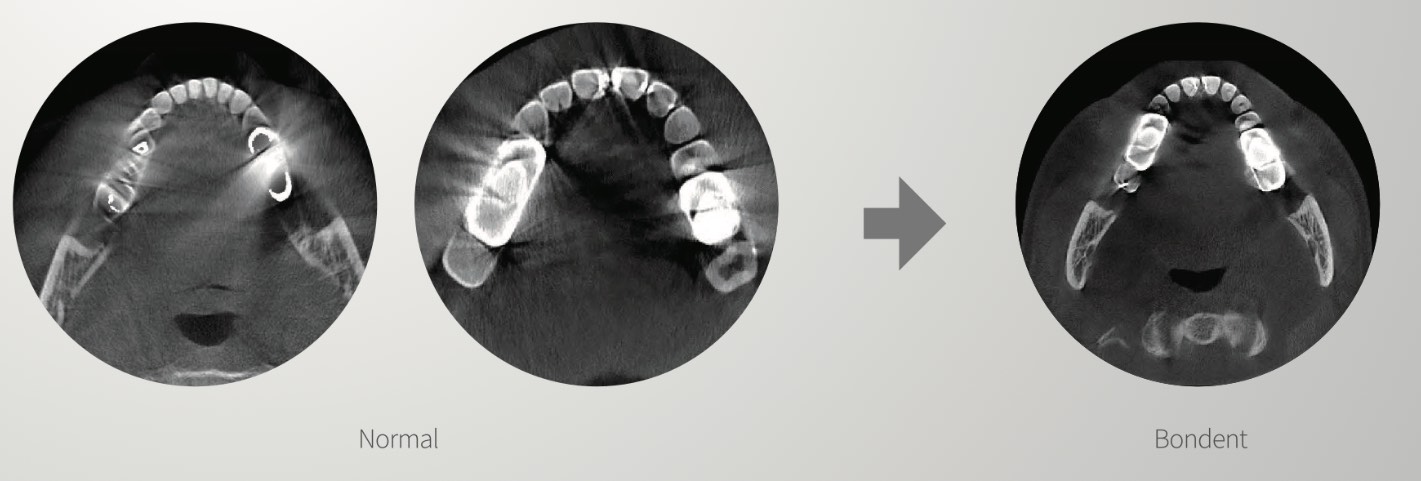

One of the most outstanding features of the Bondent CBCT scanner is the intelligent reduction of artefacts, which, as we have seen, make it difficult to obtain a correct diagnosis. In this image you can see the difference:

Other features of the Bondent 3-in-1 CBCT scanner:

- Intelligent noise reduction

- XPI's patented Al algorithm: recognises the maxillary and mandibular dental arches, and also outlines the biological curvature of the teeth automatically.

- Intelligent 3D nano. According to the morphology of the maxilla and mandible, the system automatically generates 33 slices of 0.8 mm thick panoramic CT images with just one touch.